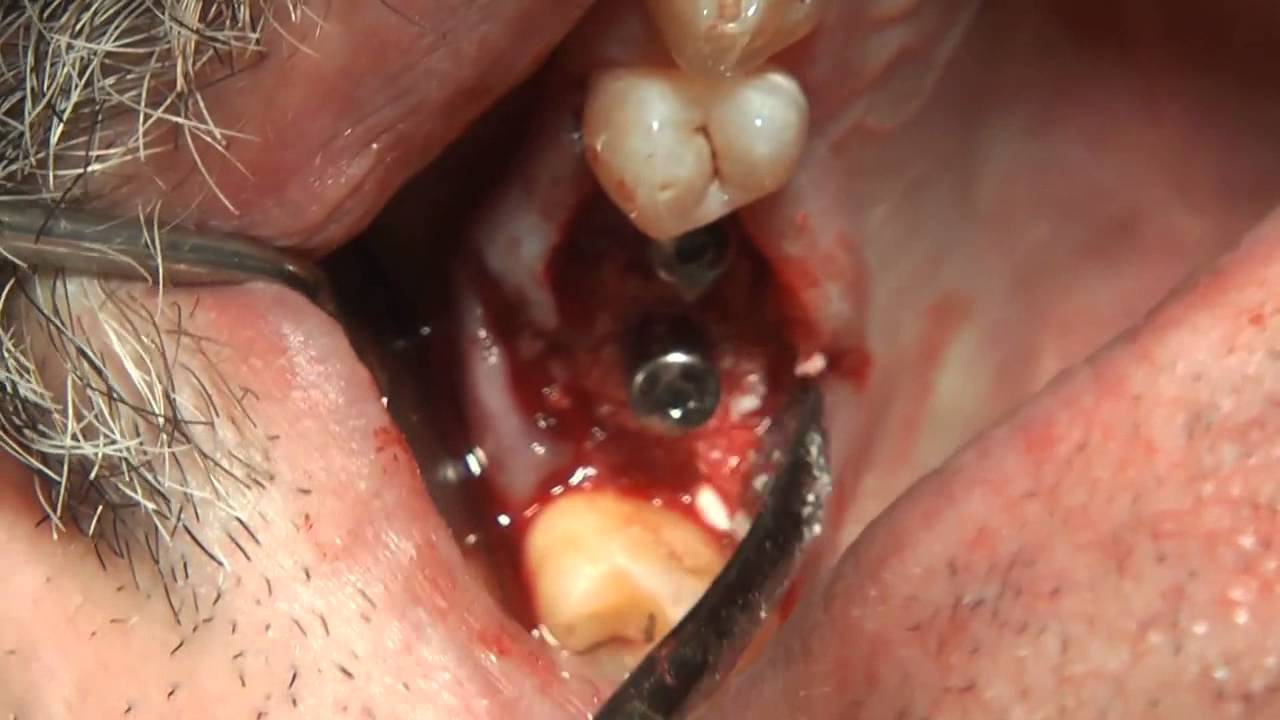

Одномоментная установка имплантата MIS SEVEN после удаления зубаОдномоментная установка имплантата MIS SEVEN implants straumann | |